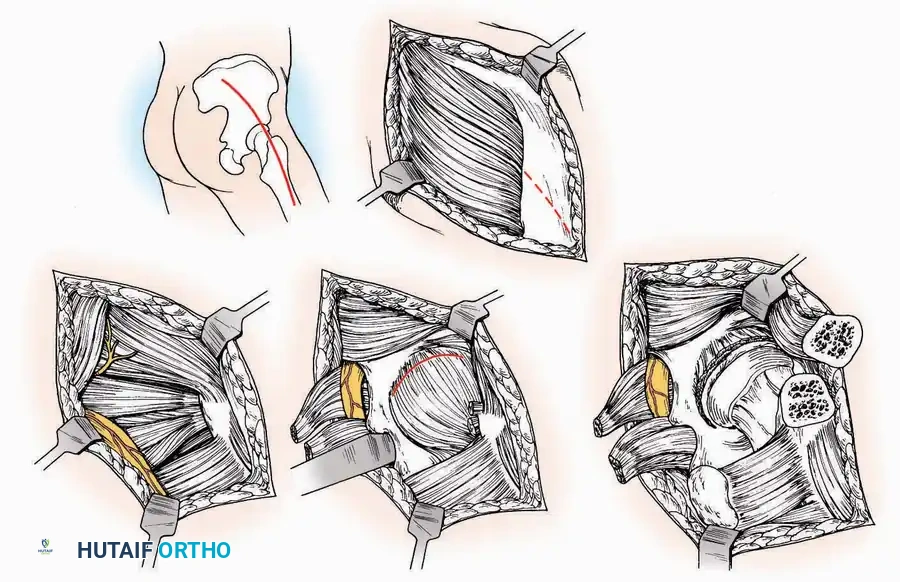

Lateral Approach (Extensile Lateral)

This is the workhorse approach for open reduction and internal fixation (ORIF) of displaced intra-articular calcaneal fractures.

Indications: ORIF of calcaneus fractures, lateral wall exostectomy, subtalar arthrodesis.

Positioning: Lateral decubitus with the operative leg up, or supine with a large bump under the ipsilateral hip to internally rotate the leg.

Surgical Technique:

* Incision: Begin the incision on the lateral margin of the Achilles tendon near its insertion. Extend it distally to a point 4 cm inferior and 2.5 cm anterior to the lateral malleolus. (For trauma, a classic L-shaped extensile incision is often used, dropping straight down anterior to the Achilles, then curving gently toward the base of the 5th metatarsal).

* Superficial Dissection: Divide the superficial and deep fasciae. It is imperative to create a "full-thickness" flap containing skin, subcutaneous fat, and periosteum to prevent flap necrosis.

* Nerve Protection: The sural nerve crosses the proximal and distal limbs of this approach. It must be identified and protected within the anterior flap.

* Deep Dissection: Isolate the peroneal tendons (longus and brevis). Incise and elevate the periosteum below the tendons to expose the lateral wall of the calcaneus.

* Tendon Management: If severe deformity or infection is present, the peroneal tendons may be divided via Z-plasty and repaired at the conclusion of the case, though this is rarely necessary in modern fracture care.